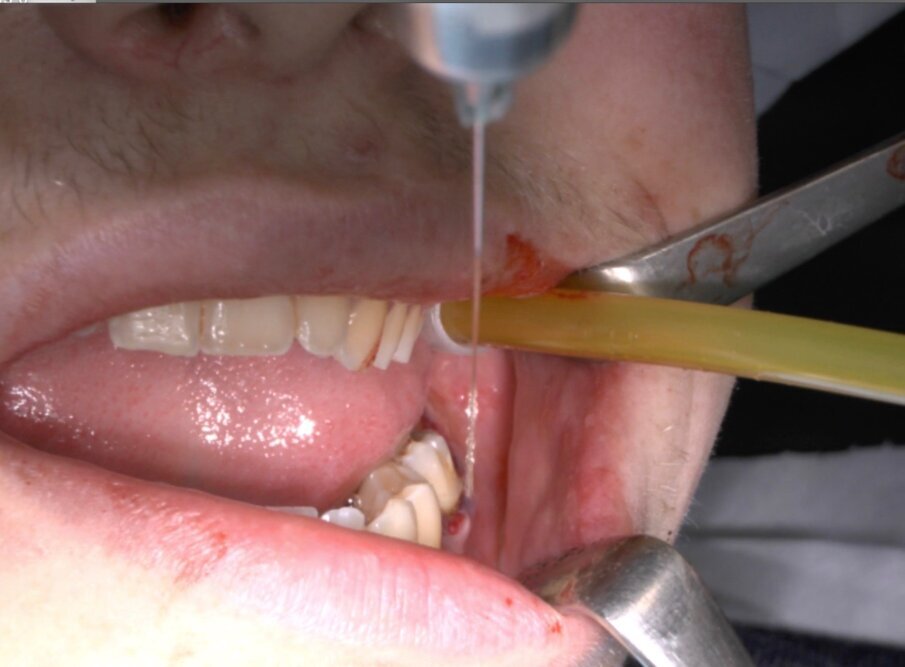

Ai pazienti viene prescritta una profilassi antibiotca con 2 gr di amoxicillina 1 h prima dell’intervento, si esegue quindi un anestesia di tipo tronculare con lidocaina senza vasocostrittore, poi infiltrazione di tipo plessica con adrenalina in corrispondenza del nervo buccinatore. Si scolpisce quindi un lembo a tutto spessore di tipo triangolare con incisione orizzontale alla base delle papille tra sesto e settimo ed incisione di scarico distale con andamento vestibolare (Figg. 1-4). Si procede con l’osteotomia che può essere eseguita con strumenti rotanti montati su manipolo retto oppure con terminale piezoelettrico con gli inserti dedicati. Qualora sia necessario si effettua l’odontotomia e la separazione radicolare con frese al carburo di tungsteno montate su turbina, quindi si esegue la lussazione e l’avulsione dell’elemento dentario. Si procede alla revisione della cavità alveolare con abbondante lavaggio con soluzione fisiologica, riempimento con collagene e sutura a punti staccati in seta 4/0. Il paziente viene dimesso con terapia analgesica ed antibiotica di supporto (Figg. 5-15).

Fig. 8_Odontotomia. Il taglio si trova fra la zona di massima circonferenza e la giunzione smalto cemento.

Fig. 9_Frattura della corona sezionata mediante leva dritta.